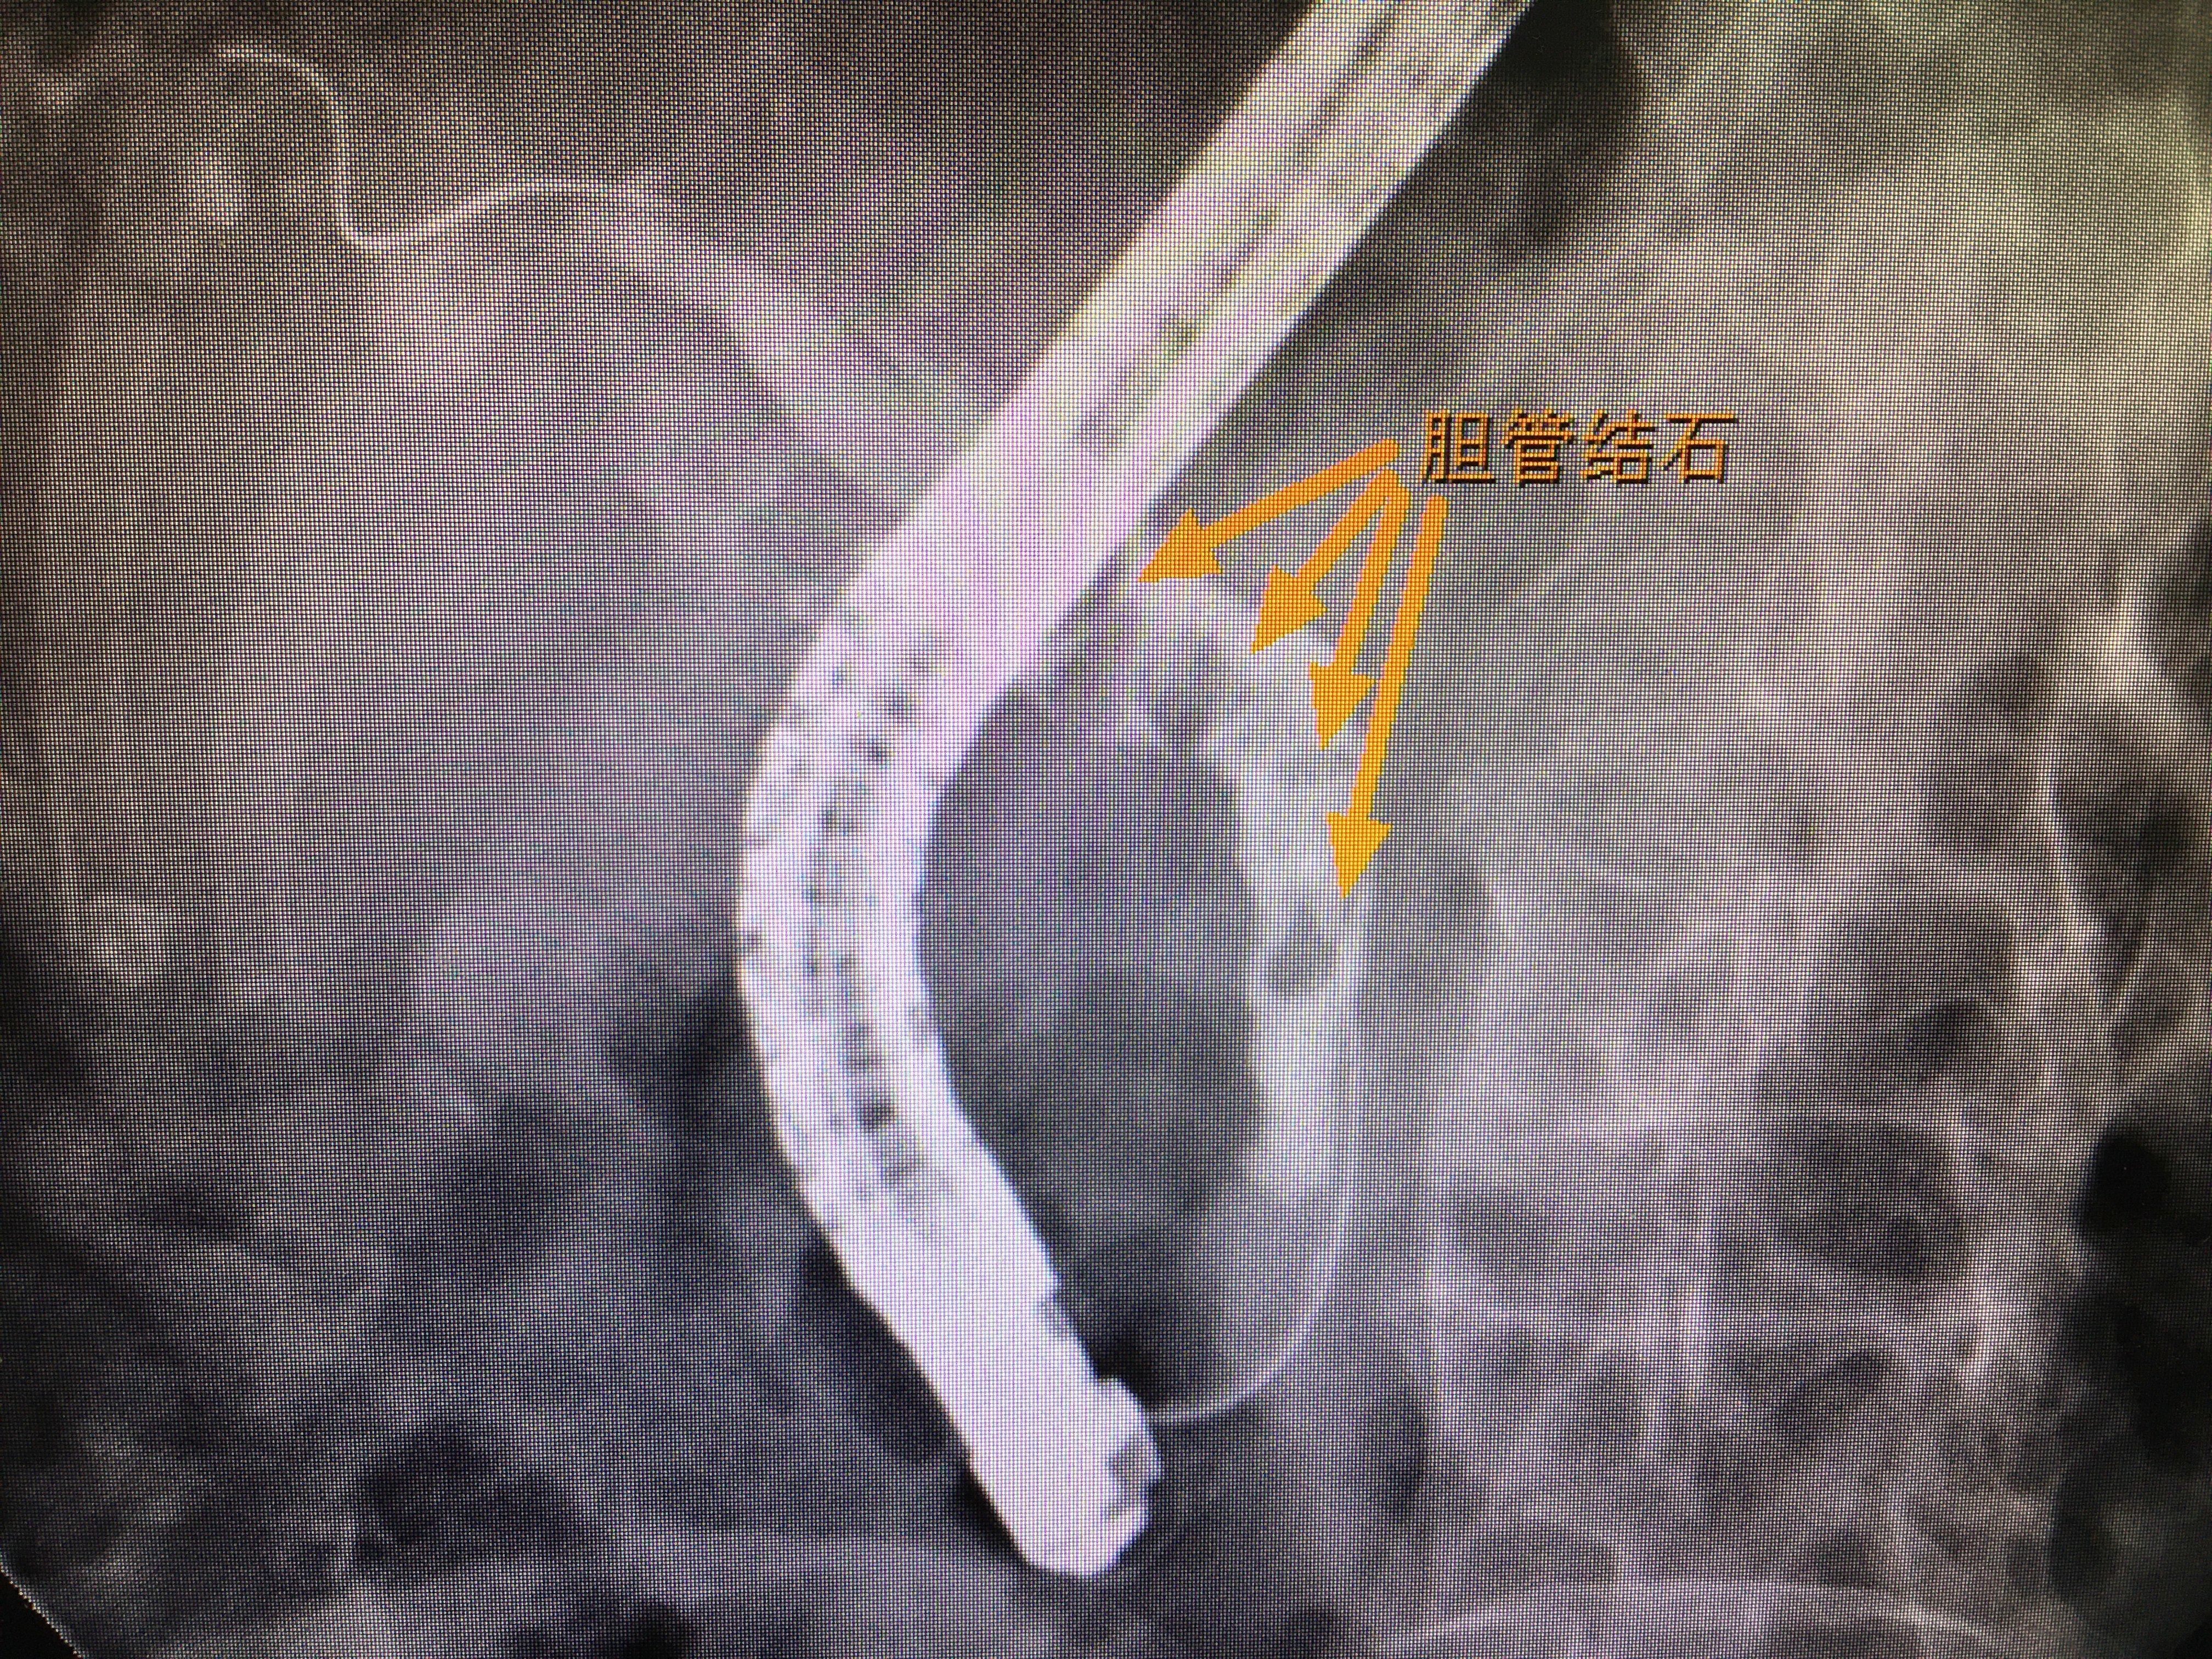

急性梗阻性化脓性胆管炎ercp快速胆管引流

图片尺寸1080x926